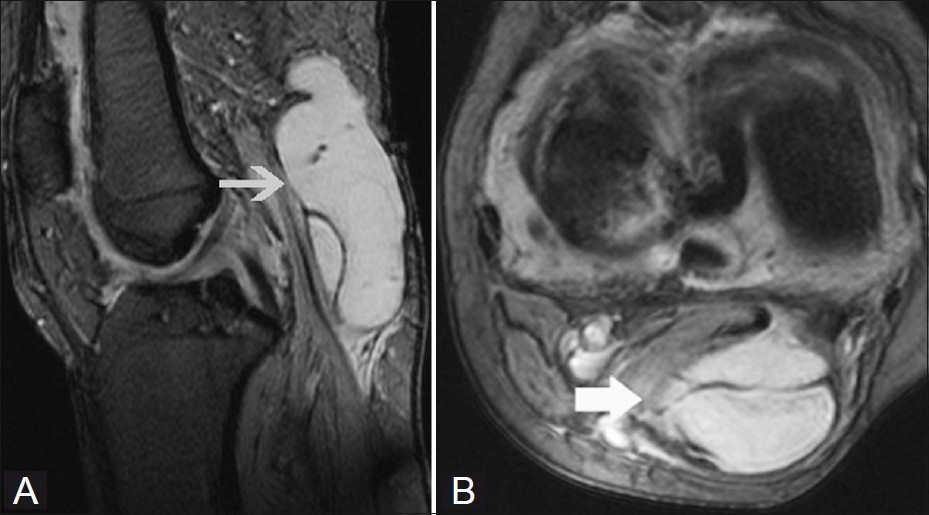

대부분의 정상적인 점액낭은 소량의 점액을 함유하여 MRI에서 잘 관찰되지 않지만, 염증성 변화에 의해 점액양이 증가되면 T1 영상에서 저신호 강도를, T2 영상에서 고신호 강도를 보이는 경계가 명확한 점액낭이 관찰된다.

△ 베이커 낭종(Baker's cyst)의 MRI 소견

(이미지 출처 : http://www.ijri.org/article.asp?issn=0971-3026;year=2012;volume=22;issue=1;spage=27;epage=30;aulast=Chatra)

하지만 슬와근 열공측측부인대 점액낭(Voshell's bursa)의 경우에는 정상 관절에서도 MRI 검사 시 흔히 나타나므로 각각 외측 반월연골판의 후각부 파열과 내측측부인대 파열로 오진할 수 있으므로 병적 상태와 감별을 요한다.